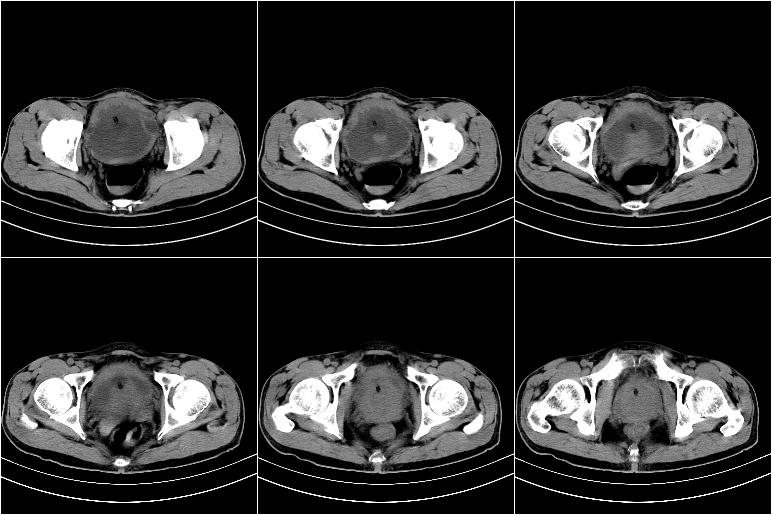

标题: CT21568:男,57岁,双肾及输尿管重度积水。彩超示前列腺占 [打印本页]

标题: CT21568:男,57岁,双肾及输尿管重度积水。彩超示前列腺占

考虑膀胱癌侵犯双侧输尿管末端及前列腺,双输尿管扩张积水。

前列腺增生肥大,内密度不均,ca不排外;膀胱壁弥漫性增厚,膀胱精囊三角清,炎症?

2 膀胱壁弥漫性增厚,内侧可见增粗的小梁和腺体,考虑为腺性膀胱炎

前列腺增生,内密度不均,警惕癌变,膀胱壁弥漫性增厚,考虑慢性膀胱炎。

考虑前列腺增生症并腺性膀胱炎,双侧输尿管扩张;建议必要时行mri检查。